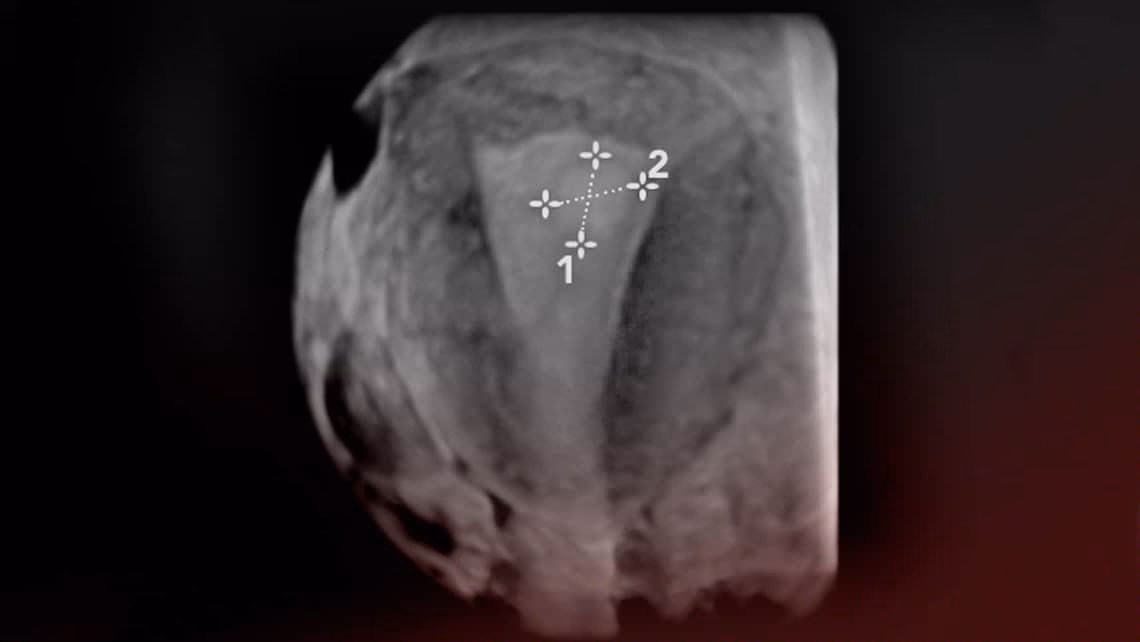

- Sonohisterografía (Histerosonografía): Este procedimiento mejora la ecografía transvaginal. Se introduce una pequeña cantidad de solución salina estéril en el útero a través de un catéter delgado antes de realizar la ecografía. El líquido expande la cavidad uterina, permitiendo una visualización más clara del revestimiento y de cualquier crecimiento, como los pólipos. Es una técnica muy útil para identificar y localizar pólipos pequeños.

- Histeroscopia: Considerada el método diagnóstico más preciso. Durante una histeroscopia, se introduce un delgado telescopio flexible o rígido (histeroscopio) con una cámara al final a través del cuello uterino hasta el útero. Esto permite al médico visualizar directamente el interior de la cavidad uterina en un monitor. Los pólipos se ven claramente y se puede determinar su tamaño, número y ubicación. Además, durante la histeroscopia, es posible tomar una muestra (biopsia) del pólipo para su análisis, aunque a menudo, si se visualiza un pólipo, se procede directamente a su extirpación.